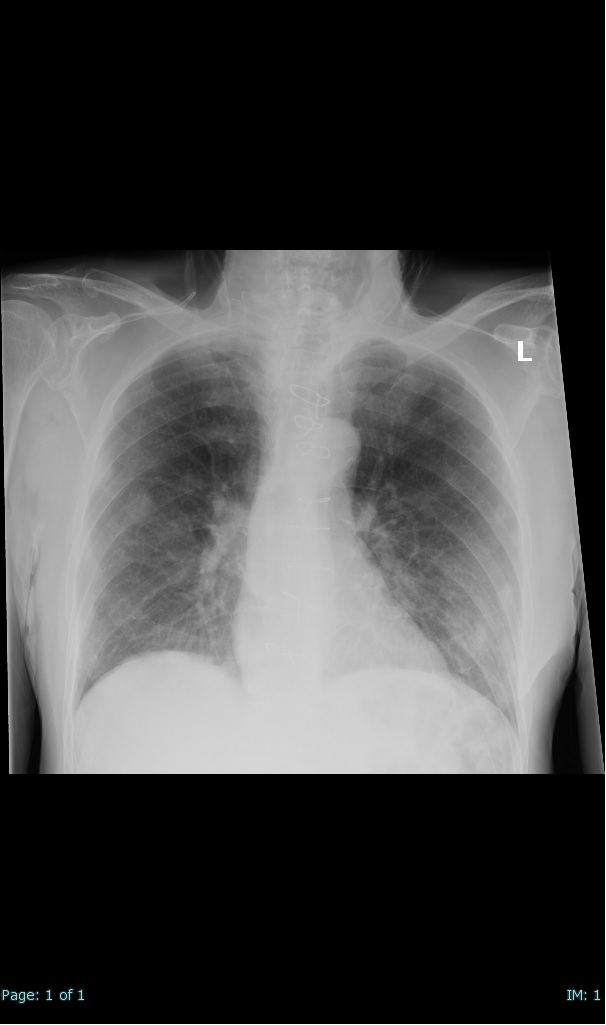

- 66% had some + CXR finding I could correlate to a CT finding

- 100% subpleural involvement, 33% + centrolobular involvement

- 40% even apical/basilar, 27% basilar dom, 5% mid dom. 1/17